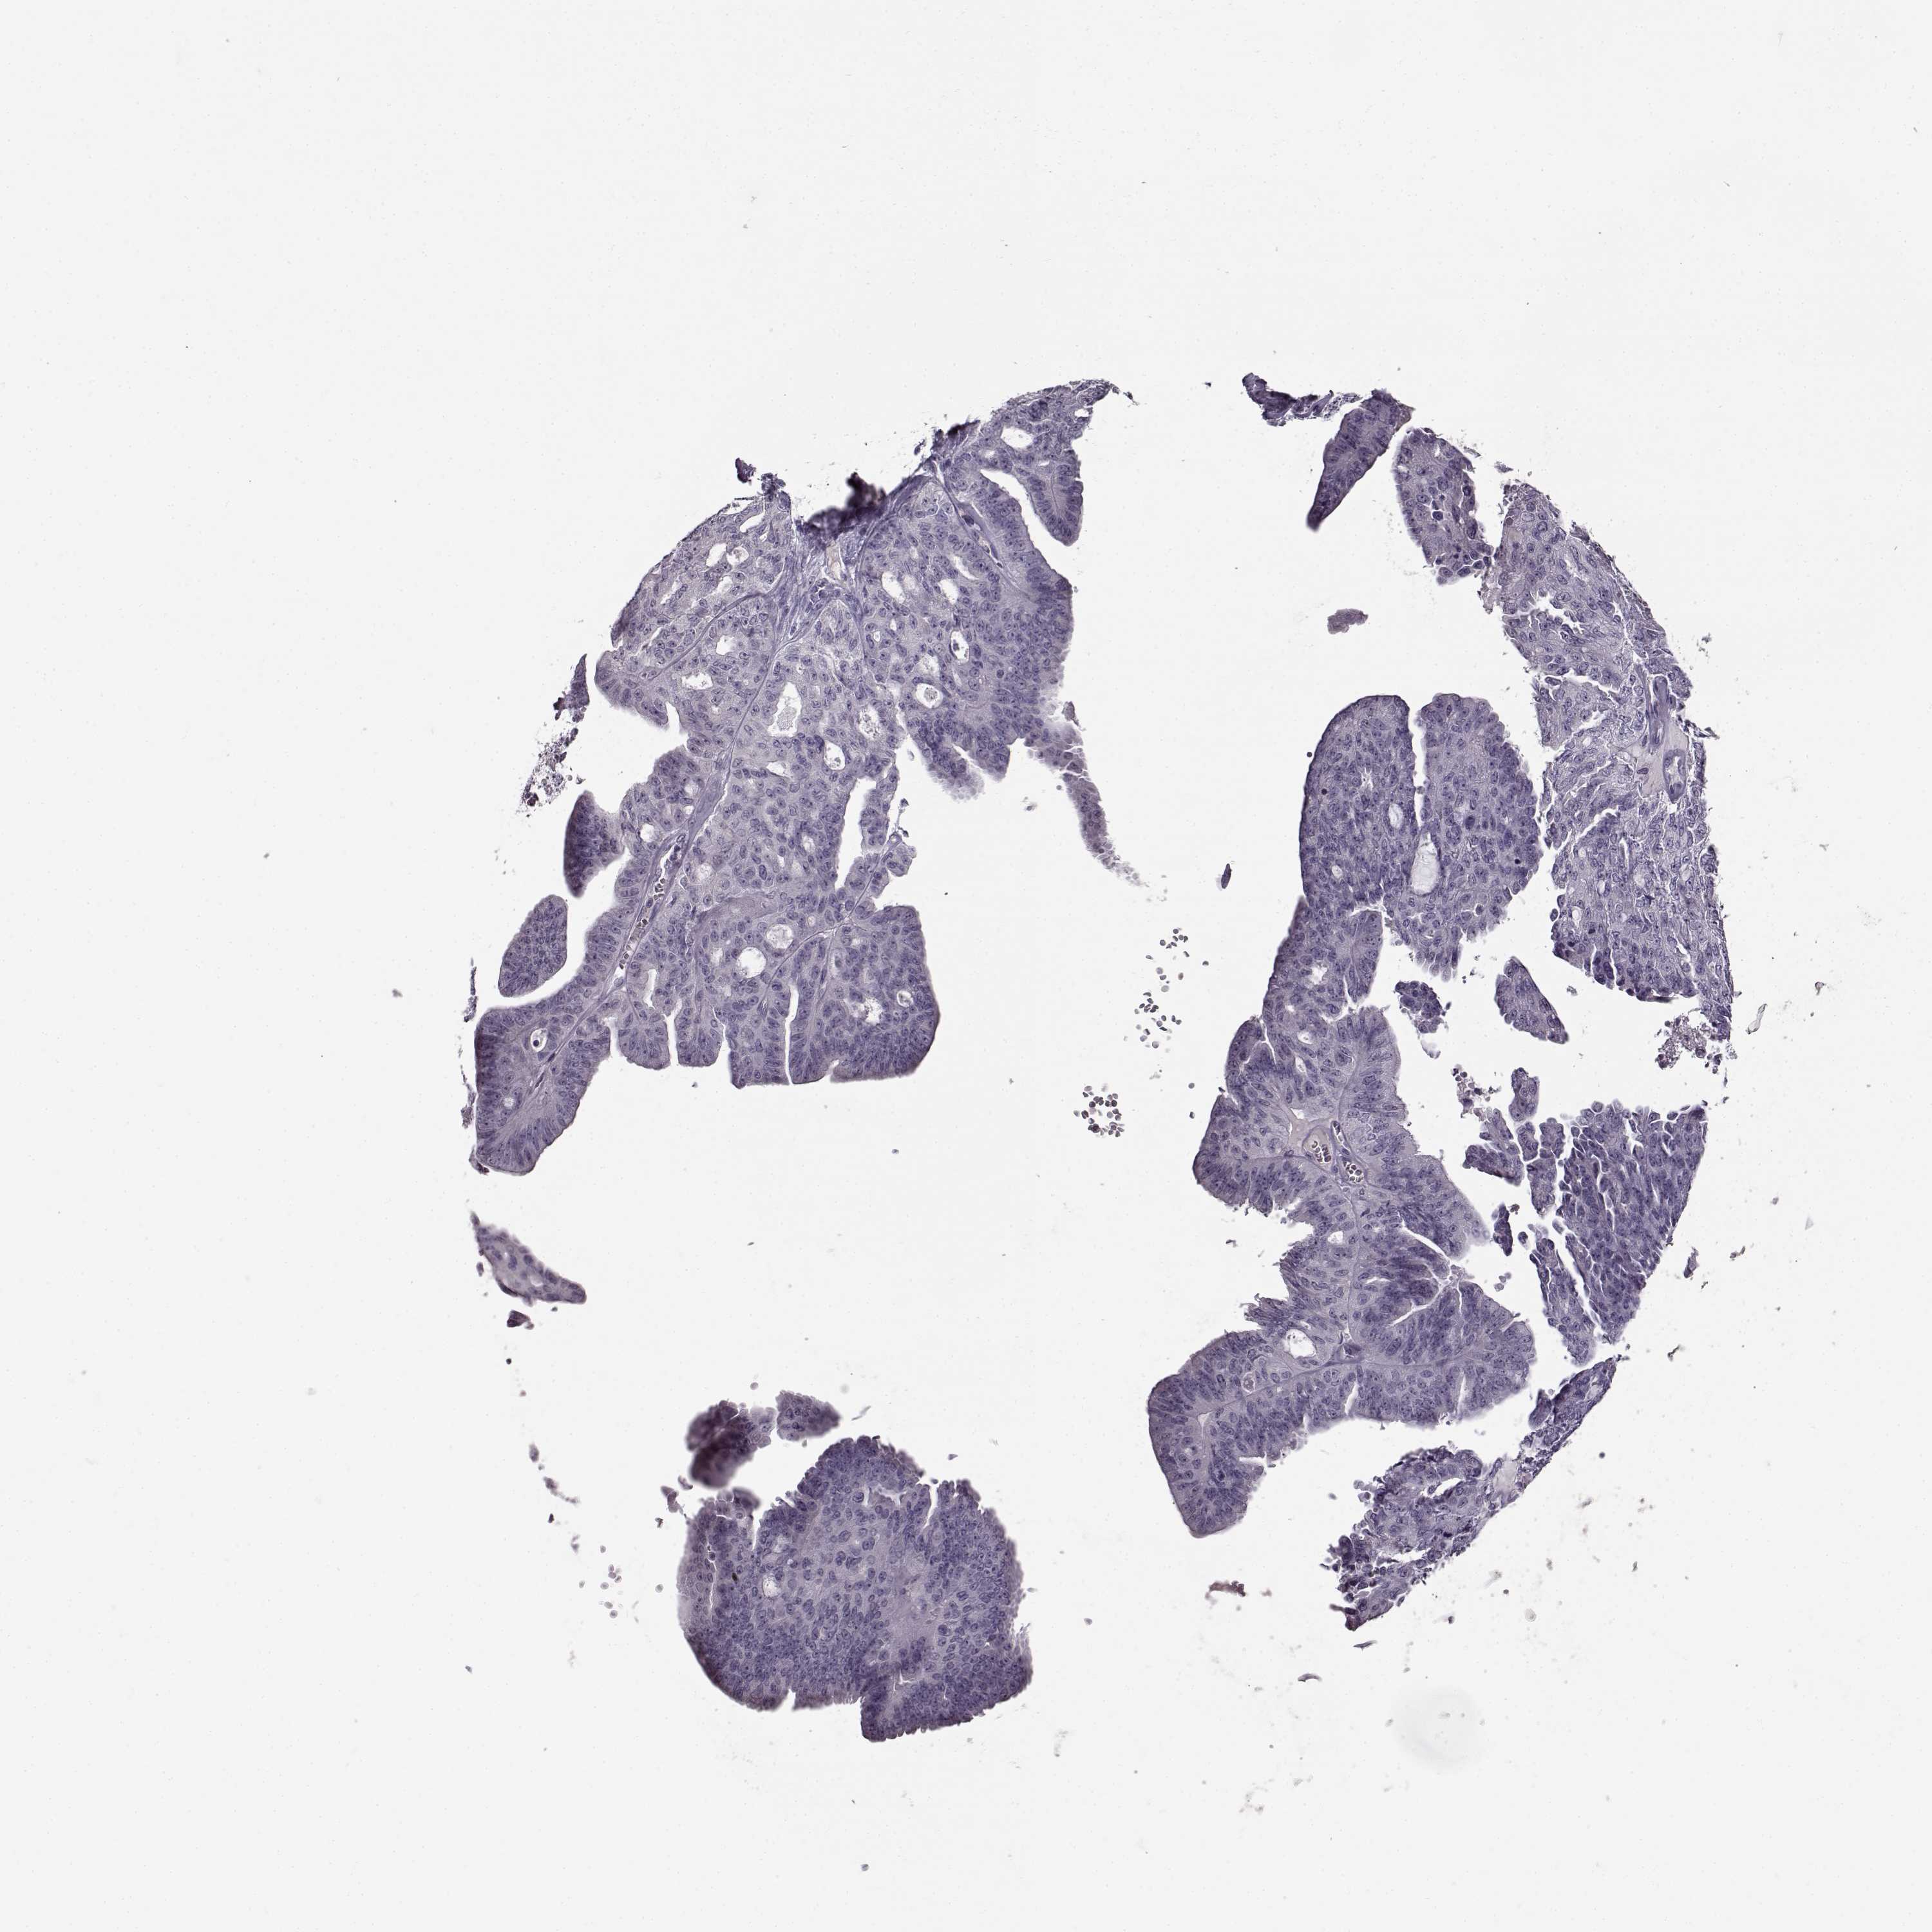

OVARIAN CANCER - Protein expressioni

A mouse-over function shows sample information and annotation data. Click on an image to view it in a full screen mode. Samples can be filtered based on level of antibody staining by selecting one or several of the following categories: high, medium, low and not detected. The assay and annotation is described here.

Note that samples used for immunohistochemistry by the Human Protein Atlas do not correspond to samples in the TCGA dataset.

Antibody stainingi

Antibody staining in the annotated cell types in the current human tissue is reported as not detected, low, medium, or high, based on conventional immunohistochemistry profiling in selected tissues. This score is based on the combination of the staining intensity and fraction of stained cells.

Each image is clickable and will lead to virtual microscopy that enables deeper exploration of all samples and also displays staining intensity scores, fraction scores and subcellular localization as well as patient and tissue information for each sample.

Antibody HPA069703

Antibody CAB023410

Staining

High

Medium

Low

Not detected

Intensity

Strong

Moderate

Weak

Negative

Quantity

>75%

75%-25%

<25%

None

Location

Nuclear

Cytoplasmic/membranous

Cytoplasmic/membranous,nuclear

Cystadenocarcinoma, serous, NOS

Cystadenocarcinoma, mucinous, NOS

Carcinoma, endometroid